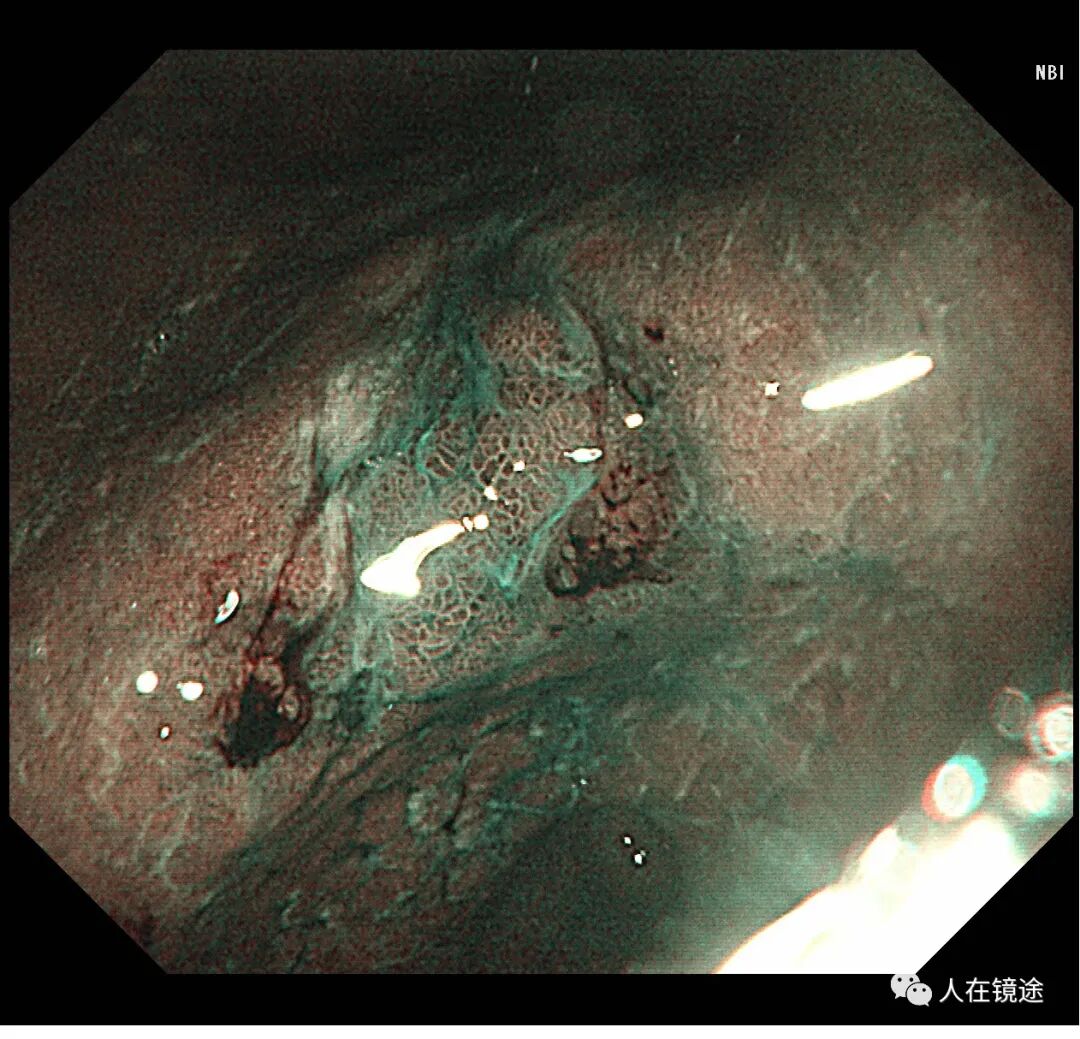

NBI示:胃窦小弯见一0.8*1.2cmIIa粘膜病变呈咖色,边界清楚,表面粘膜高低不平伴自发性出血。

NBI+近焦示:胃窦小弯见一0.8*1.2cmIIa粘膜发病变呈咖色,边界清楚,微结构紊乱,表面粘膜高低不平伴自发性出血